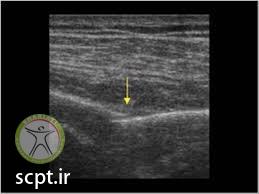

معمولاً در ناحیه آسیب دیده کبودی قابل مشاهده است. تشخیص قطعی توسط x-ray و سی تی اسکن و اسکن استخوانی امکان پذیر است. همچنین از MRI نیز برای مشاهده بافت های نرم و اندام های اطراف دنده ها مانند ریه استفاده می شود.